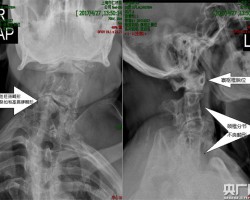

- 仁济医院完成首例3D打印辅助救治复杂颈椎畸形脱位患者

0评论2017-06-03